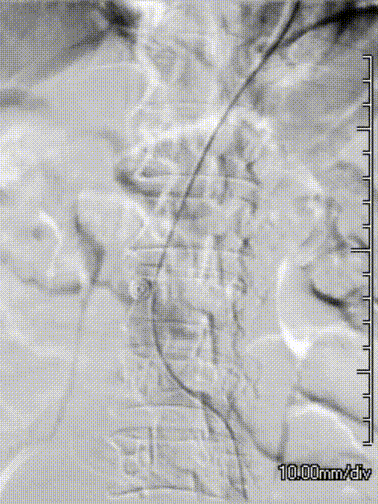

14. 释放C3主体长腿侧,并造影确认髂外桥接长度,随后左侧桥接髂支PLC141400,锚定于左侧髂总远端,进行球囊后扩支架近远端及桥接部位。

gore医疗怎么样「漫腹精论」髂合时宜 精益求精——双MOB球囊导管辅助腹主动脉覆膜支架急诊治疗破裂巨大髂动脉瘤_https://www.jmylbn.com_新闻资讯_第24张

15. 造影确认支架密封效果等等。

17. 后扩后再次进行造影,瘤体未见显影,双侧肾动脉,左侧髂内动脉,双侧髂外动脉通畅,结束手术。

gore医疗怎么样「漫腹精论」髂合时宜 精益求精——双MOB球囊导管辅助腹主动脉覆膜支架急诊治疗破裂巨大髂动脉瘤_https://www.jmylbn.com_新闻资讯_第27张